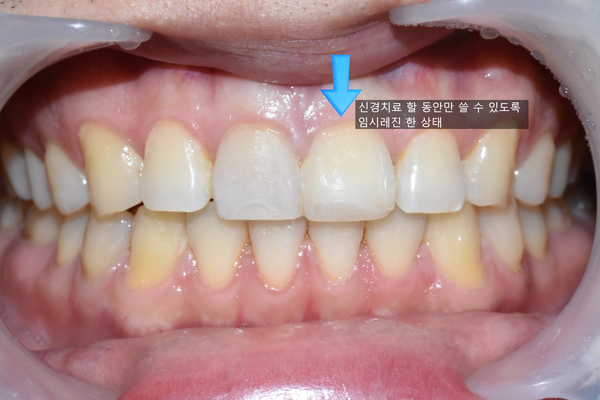

깨진 앞니(좌측사진), 깨진 앞니에 한 임시 레진(우측사진)

오른쪽 치아는 신경치료도 진행해야 하는 상황이라 신경치료를 하는 동안 마스크를 쓰지 않고도 사회생활을 할 수 있도록 오른쪽 사진처럼 임시로 레진을 해놓아서 다행히 크게 티나지 않게 환자분이 사회생활을 할 수 있었습니다.

임시는 말그대로 임시라서 완벽하거나 이쁘지는 않습니다.

임시로 단기간만 쓸 레진을 한 상태